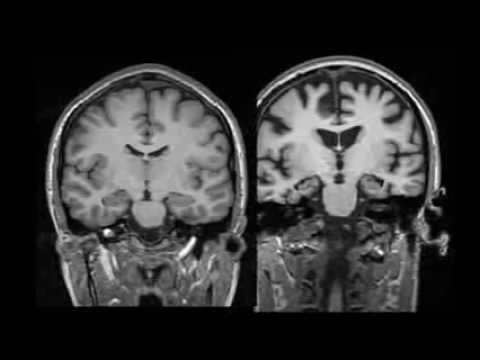

Segredos do Cérebro. Tanto para descobrir!

"Os próximos anos testemunharão novas e empolgantes descobertas sobre os nossos cérebros - desde a criação de melhores ferramentas para aprofundar a mente até a criação de nanobots inteligentes".